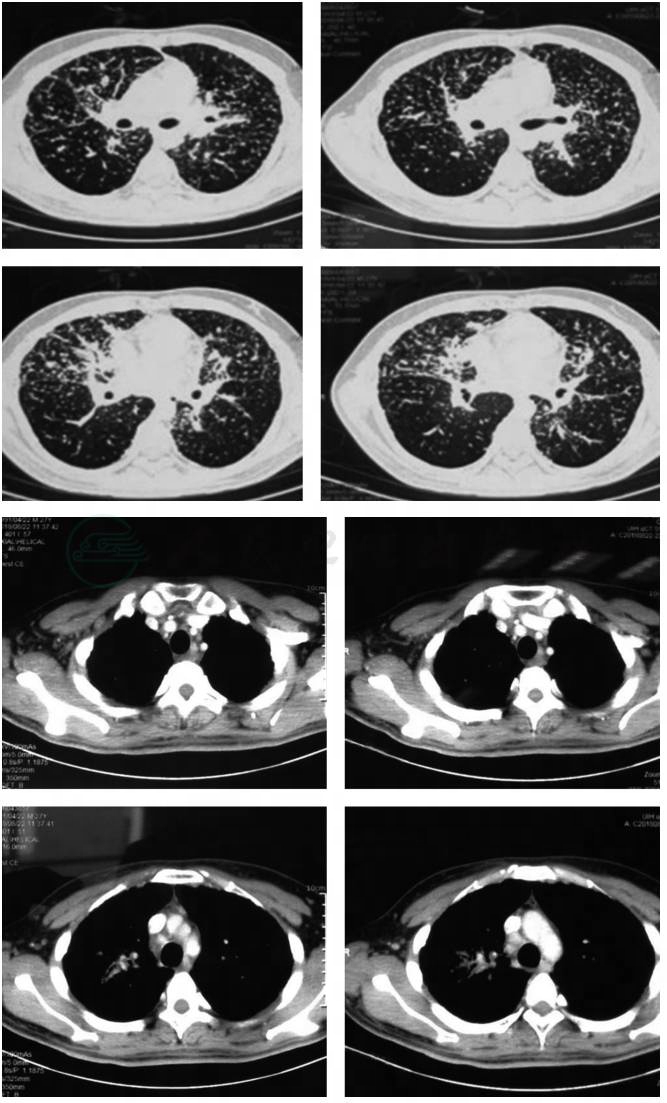

胸部CT(2017年3月)两上肺结节及斑片影,纵隔及双侧肺门淋巴结肿大(图1)。

肺部CT(2018年8月)双肺结节及斑片影较前明显增多,但纵隔和双肺门淋巴结较前缩小(图2)。

图1 肺部CT 2017年3月

图2 肺部CT 2018年8月